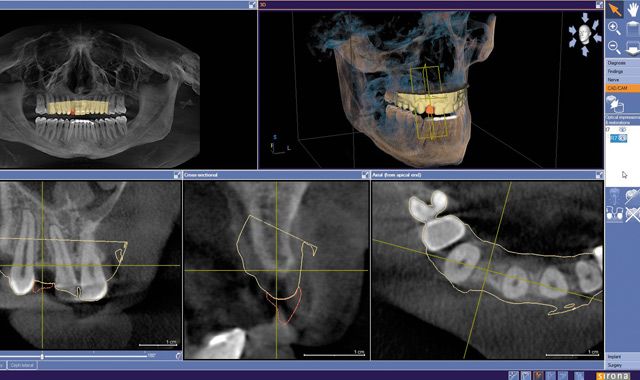

Fig. 08 Integrated implant treatment planning software allows the clinician to virtually plan implant placement in 3D.

Fig. 09 A cross-sectional image showing the integrated CAD/CAM virtual restoration with the planned implant.

Fig. 10 A volumetric analysis of comprehensive implant planning.